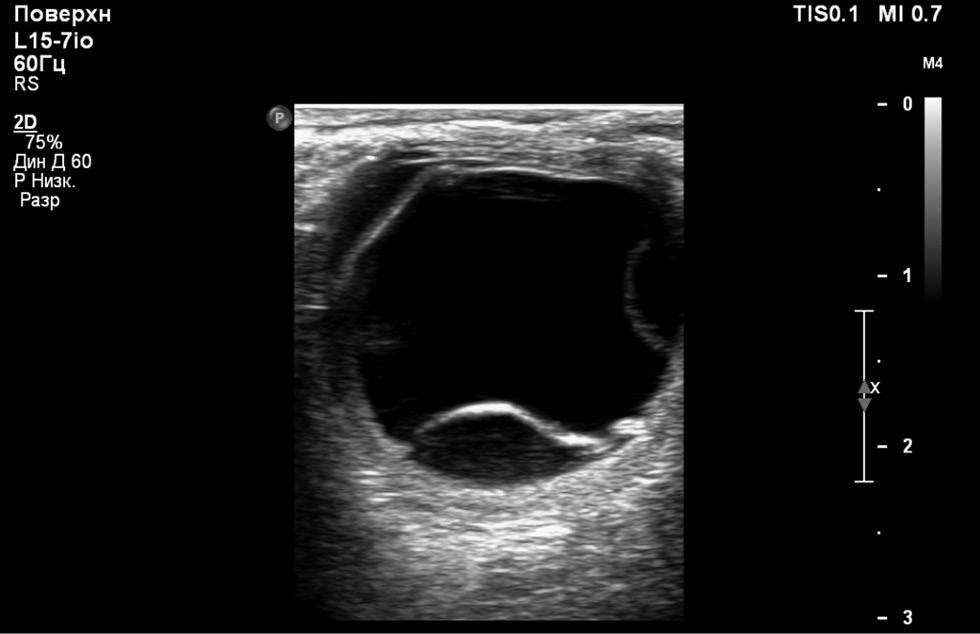

RESULTS: This article presents the clinical case of postoperative choroidal detachment in a child with Sturge–Weber–Crabbe syndrome after microinvasive non-penetrating glaucoma surgery. Against the background of the existing anomalies in the development of an optic disc after antiglaucomatous intervention for decompensated glaucoma, after the normalization of IOP, the patient developed choroid detachment with exudative retinal detachment the next day of operation. After conservative therapy involving bed rest and double instillation of mydriatics for 1 month, the situation was completely resolved and his vision was restored to 1.0.

DISCUSSION: The atypicality of our clinical case of CD lies in the overly pronounced exudative component. In addition to the classic CD vesicles, we observed high exudative retinal detachment as well as high retinoschisis, which is extremely atypical for classical CD. Considering the characteristics of congenital syndrome, it is necessary to accurately differentiate atypical CCA from the rare choroidal effusion syndrome, which also includes CCA with retinal detachment, but does not present with retinoschisis. Against the background of conservative therapy with bed rest and two instillations of mydriatics for 1 month, the situation was completely resolved, and the patient’s vision was restored to 1.0. In the treatment of such patients, it is always necessary to consider their individual anatomical features as well as to understand the detailed pathogenesis of the complications that arise before rushing to repeat surgery.